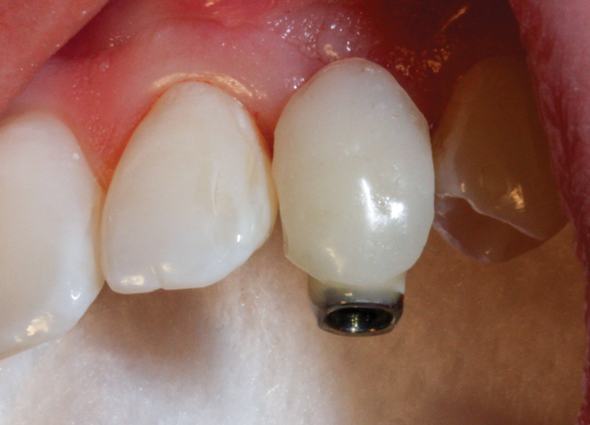

(50.) An opaqued titanium abutment was placed on the implant, and the natural tooth shell was then bonded to the abutment with flowable composite in the incisal half.

Figure 50

(51.) Palatal view of the partially completed natural tooth provisional restoration after it was removed from the mouth.

Figure 51